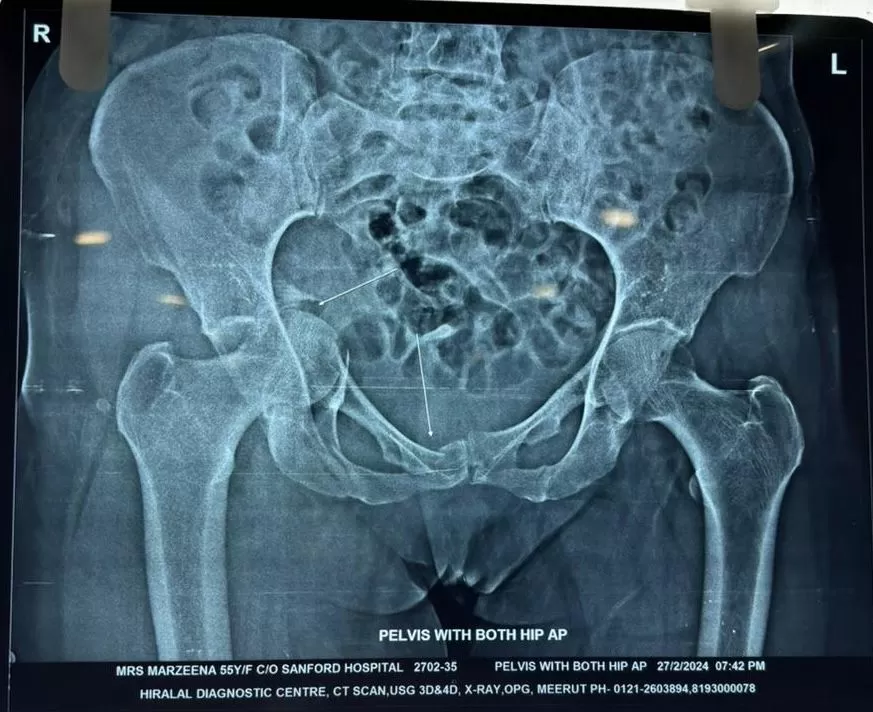

Mrs. Marzeena

Name: Mrs. Marzeena

Date of Operation: 03 Mar 2024

Age: 53 Years